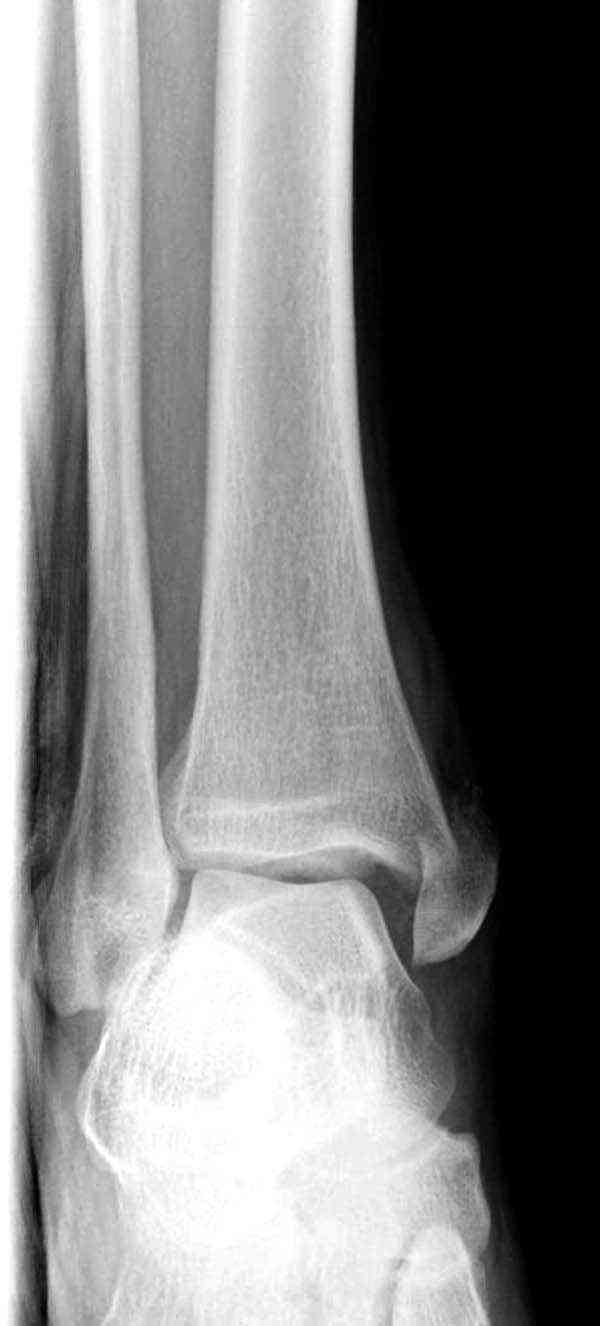

Нет первичных снимков, перелом очень низкий и под большим сомнением диагноз разрыва синдесмоза. Медиальная сторона отрепонирована на "хорошо" и, по-видимому, прорезание проволоки произошло во время операции. Без снимков трудно судить о высоте малоберцовой, а лодыжка находится в варусе. Лагирование получилось, но возле тонких шурупов передне-задний шуруп выглядит немного тяжеловато.

Коллеги правы, что при рутинных переломах достаточным бывает обычные снимки с мортизом. А стрессовые рентгенограммы могут уточнить, есть ли разрыв синдесмоза.

Здесь несколько частных случаев: перелом голеностопа со сравнительными снимками и разрыв синдесмоза, а также медиальная Hook пластина.